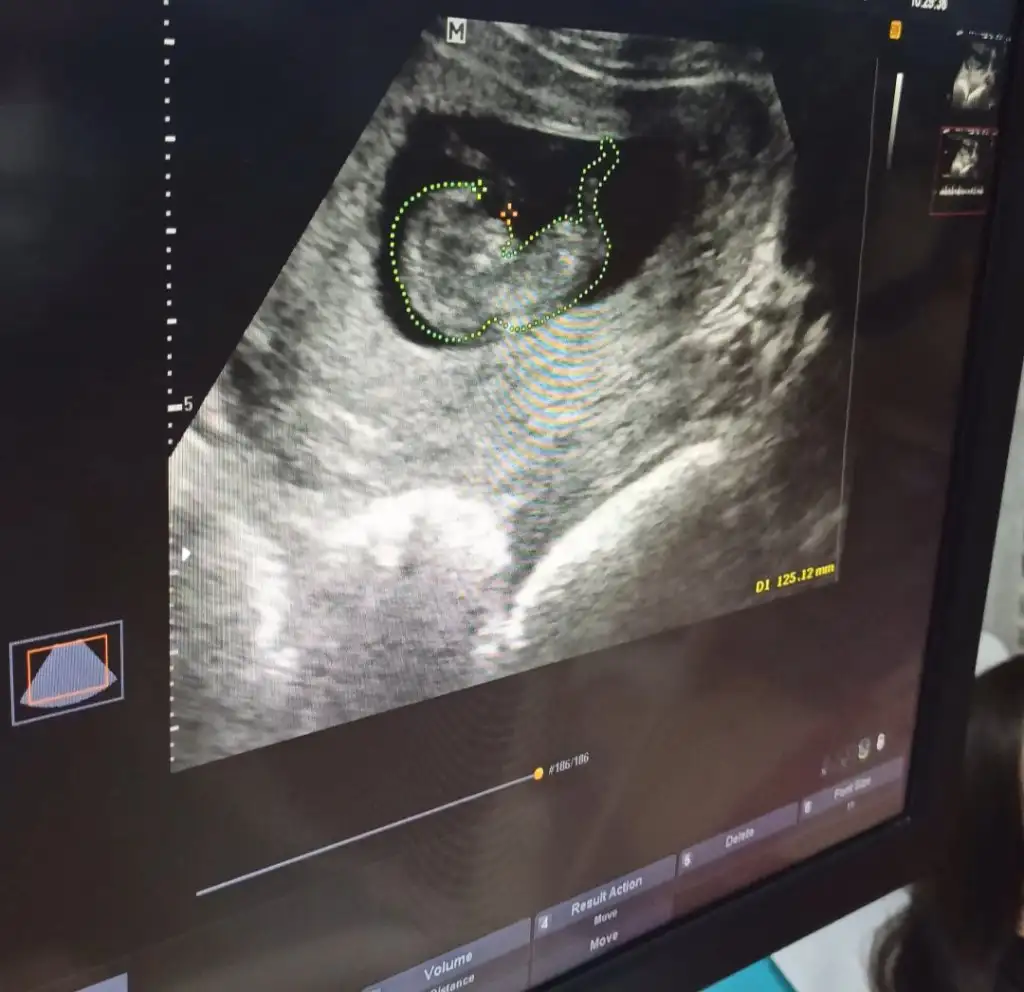

Yükledim hepsini şimdi canım. Nub görünen foto da var.Emin değilim ama sanki erkek gibi başka USG varsa paylaşın

Emin değilim ama sanki erkek gibi başka USG varsa paylaşınMerhaba benimkisi 12 haftalık tam. Bakar mısın lütfen. Doktor 10. Haftada erkeğe benzetti ama bugün de kız gibi dedi :)